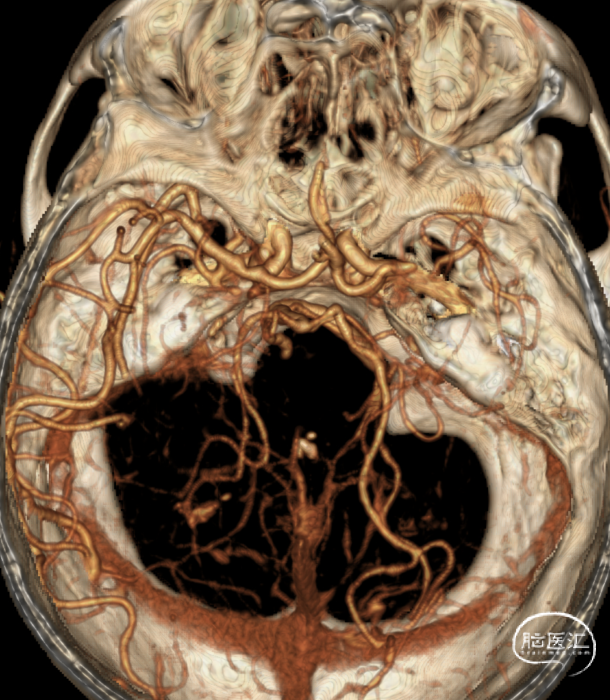

➢术前CTA

4.CTA、MRI、DSA证实右侧大脑中M1闭塞,闭塞长度<1cm。